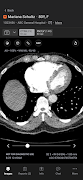

Aplikasi komunikasi mudah alih Aidoc memperkemas komunikasi untuk mempercepatkan membuat keputusan sensitif masa dan meningkatkan kualiti penjagaan. Aplikasi ini menyediakan keutamaan berasaskan AI dan pemberitahuan pelbagai jenis patologi akut termasuk oklusi saluran besar dan embolisme pulmonari.

AI Sentiasa Hidup Aidoc secara automatik mengambil dan menganalisis setiap peperiksaan yang berkaitan untuk mengenal pasti penemuan yang disyaki. Setelah peperiksaan dibenderakan, Aidoc kemudian menyerlahkan penemuan yang disyaki secara langsung dalam aliran kerja pengimejan perubatan. Proses ini memanfaatkan infrastruktur sedia ada dan beroperasi dengan lancar di latar belakang, memproses beribu-ribu peperiksaan setiap hari. Aidoc membantu mengurangkan masa daripada imbasan kepada diagnosis, mempercepatkan kecekapan, masa untuk rawatan dan meningkatkan kualiti penjagaan.